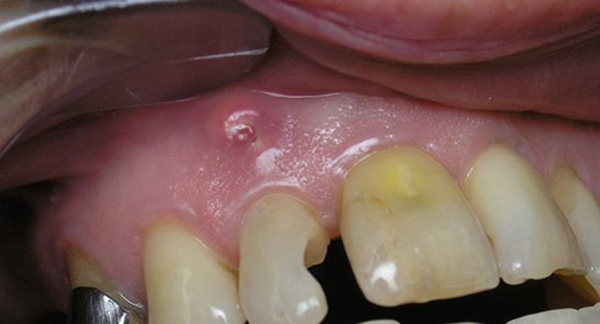

Попадание микробов в пульпу приводит к возникновению различных воспалительных процессов, в том числе пульпита, периодонтита. Скопление гноя в прилежащих тканях может принимать форму гранулёмы, флюса, а если организм не сможет ограничить очаг гнойного воспаления, то развивается флегмона.

Фото 2. Гранулема с гноем на десне, образуется из-за попадания микробов с эмали внутрь зуба.

Эти воспалительные процессы опасны для человека в силу близкого расположения челюстей к магистральным кровеносным сосудам и головному мозгу. Прорыв гнойного содержимого может привести к самым негативным последствиям, вплоть до того, что можно умереть.